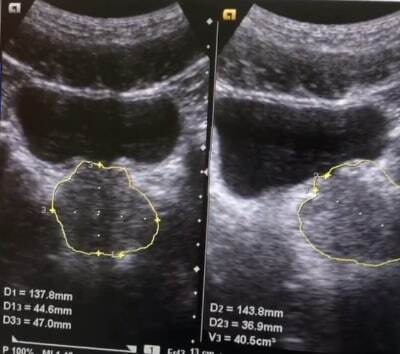

На прилагаемом изображении показан результат УЗИ простаты у мужчины, которому всего 28 лет 🤷🏻♂️